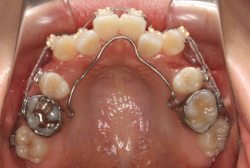

ネックバンドを1年半使用して、上顎大臼歯が十分後ろに下がったところで、裏側にリンガルアーチという固定のワイヤーを取り付けて、新しく生じた隙間が狭くならないよう「保隙(ほげき)」という処置をして、永久歯が生えそろうまで待機中の様子です。配列全体に隙間が生じているのがお分かりいただけると思います。これだけの隙間が確保できていれば、抜歯をしなくても、あとで上の前歯を内側に理想的な角度で引っ込めることができます。このように完全に永久歯列になる前に、十分な隙間が確保できるかどうかが、非抜歯で矯正できるかどうかの分かれ目になります。